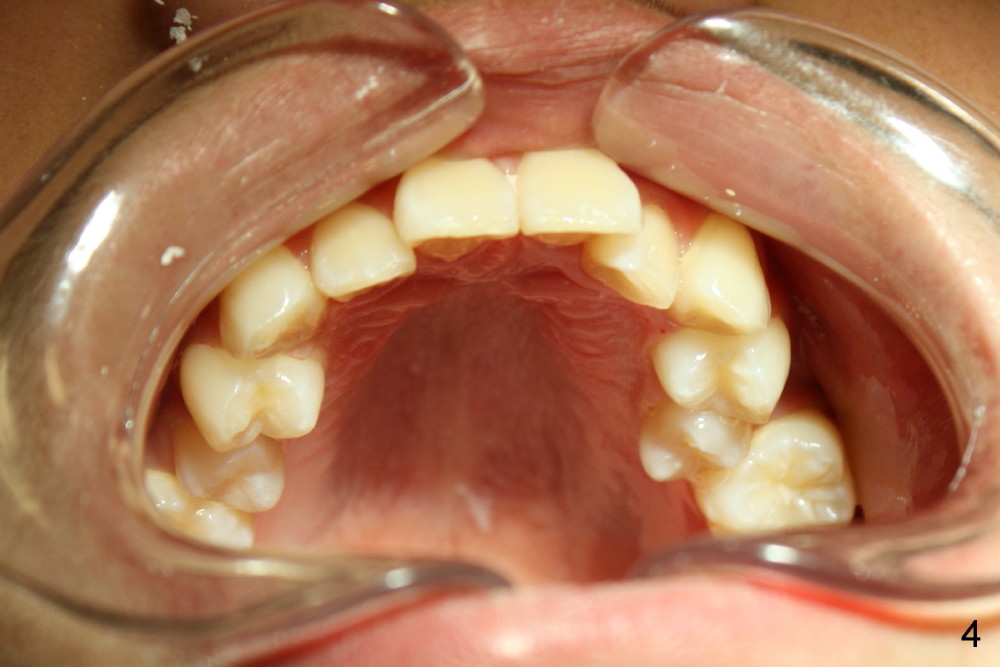

A 13-year-old boy has severe crowding (Fig.1-5). Four of the first bicuspids were extracted on 02/17/2014. Full mouth brackets or bands (except #18) were placed on 03/27/2014. Alignment improved 2 months later (Fig.11, 05/24/2014). The upper 18 ss wire was modified (Fig.12), and fixed with alastiks (Fig.13,14). One month later (07/01/2014), local alignment also improved (Fig.15); the upper modification is confined to one tooth.